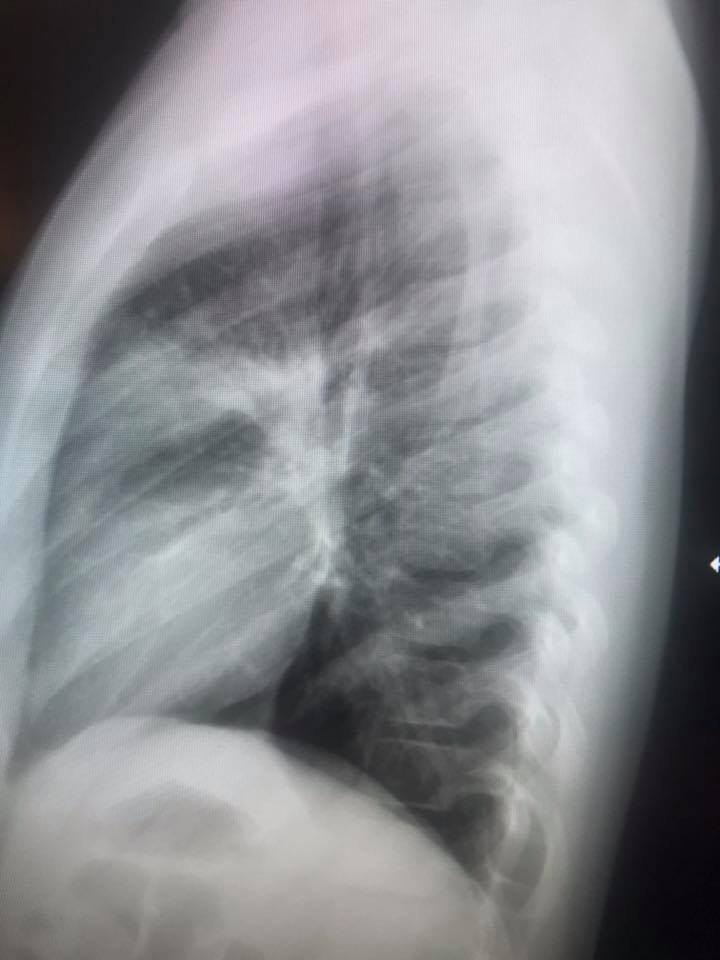

Ну и, чтобы закончить тему, кто желает получше разбираться в рентгенограммах грудной клетки, рекомендую книгу

Заказал, еще не пришла, но доктор Белозерова плохого не посоветует